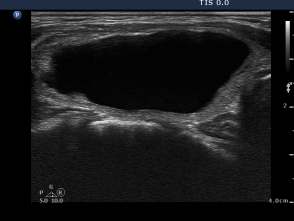

Third session of sclerotherapy (fourth row of images):

The lesion decreased in size. After removal of 2 mL bloody fluid we injected 4 mL ethanol.